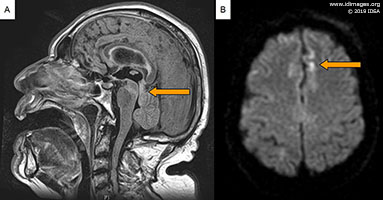

The patient was switched to intravenous liposomal amphotericin and flucytosine on day 3 after serum cryptococcal antigen showed positivity. Acyclovir was changed to ganciclovir given initial concern for CMV infection (later discontinued after CMV PCR was negative on CSF). The EVD was removed after 5 days, showing normal intracranial pressure. Subsequently, serial CT scans of the head were done which showed no progression of the hydrocephalus. Unfortunately, the patient’s neurological function continued to deteriorate. Repeat MRI of the brain after 14 days of treatment revealed findings consistent with multiple scattered ischemic lesions throughout both cerebral hemispheres, corpus callosum, deep white matter, subcortical white matter and cortex with involvement of dorsal midbrain (Figure 4a and b). He died shortly after.

- Figure 4: Follow up MRI brain without contrast at 14 days. (A) Sagittal FLAIR images showing scattered areas of hyperintensity in corpus callosum, deep white matter, subcortical white matter and cortex. (B) Diffusion-weighted imaging showing high-signal areas in both cerebral hemispheres and cortex. There was no definite corresponding apparent diffusion coefficient changes.